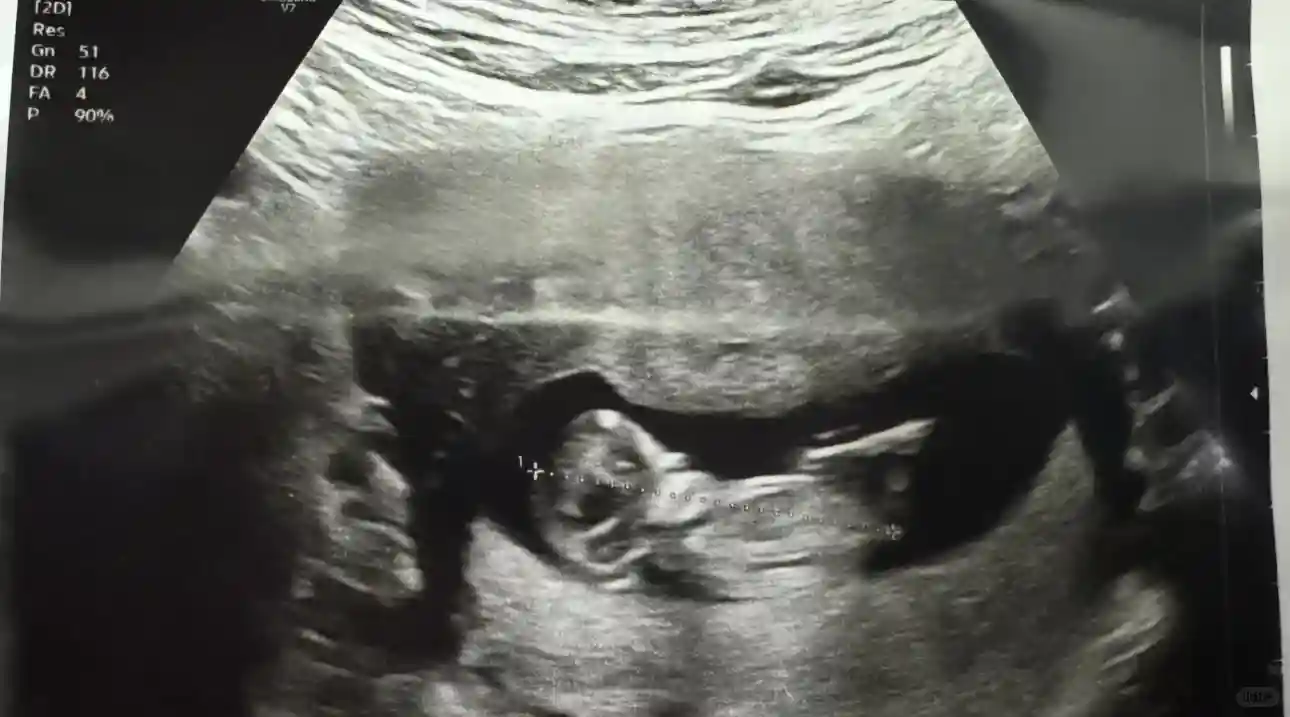

还顺便搞个Gender Reveal 是GuGu Bird 😂,可以收工了。